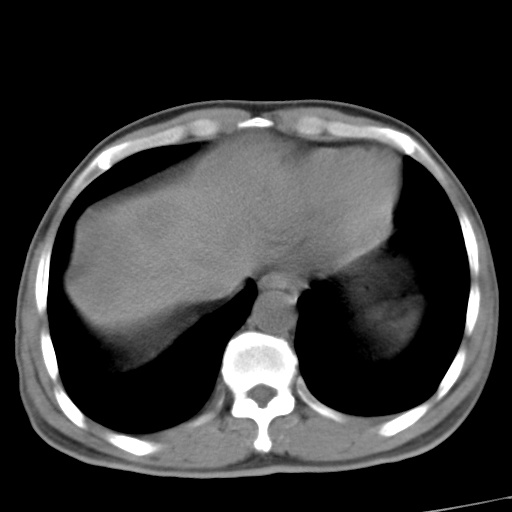

标题: CT17975:请求会诊。男、57岁。上腹部胀痛2天。临床诊断:糜 [打印本页]

标题: CT17975:请求会诊。男、57岁。上腹部胀痛2天。临床诊断:糜

肝脏多发类圆形低密度影,考虑肝脏转移瘤,肝胃韧带一淋巴结肿大,原发?胃癌?

考虑胃癌并肝脏及腹膜后淋巴结转移;不排除淋巴瘤。

肝内转移瘤,腹腔及腹膜后淋巴结转移。